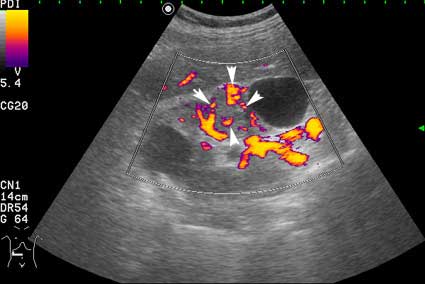

- Сканирование в режиме энергетического доплера.

Вас не смущает наличие внутреннего кровотока в одной из "кист"?

В данном конкретном случае разница есть и она довольно существенная. Все-таки образование представленное на этой странице изо- или нормоэхогенное. В Вашем случае образование имеет повышенную эхогенность, примерно равную эхогенности окружающей почку клетчатки, что в пользу именно AML.

Но Вы правы в том, что могут быть трудности в дифференциальном диагнозе между AML и RCC малых размеров (в 20-30 % случаев могут быть эхогенными). Однако при УЗИ для RCC характерен гипоэхогенный ободок, внутриопухолевые включения, низкорезистивный внутриопухолевый кровоток.

Гипоэхогенный ободок, если очень постараться, можно найти на фото 1. Внутриопухолевые включения отсутствуют в обоих случаях. Могу согласиться только на низкорезистивный внутриопухолевый кровоток (в AML он действительно отсутствовал, хотя этого я нигде не отмечал).